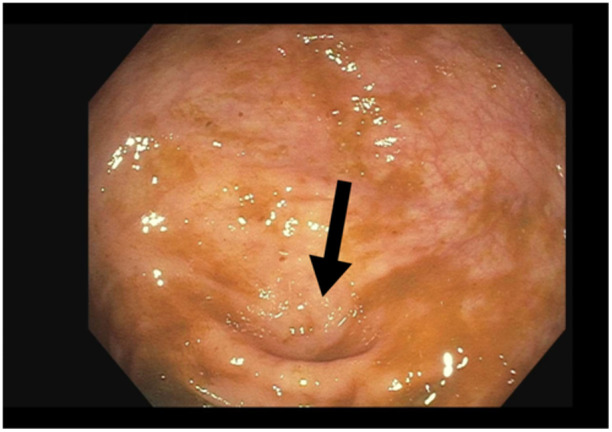

无症状阑尾炎的偶然诊断是非常罕见的,当内窥镜诊断时更是如此。这是第一个报告的病例阑尾炎偶然诊断期间结肠镜检查的儿科患者。最值得注意的是,亚临床阑尾炎的识别允许早期转介到儿科外科进行治疗,这反过来可能防止进展为急性症状性阑尾炎。

Incidental diagnosis of asymptomatic appendicitis is exceptionally rare, even more so when identified endoscopically. This is among the first reported cases of appendicitis incidentally diagnosed during colonoscopy in a pediatric patient. Most notably, the identification of subclinical appendicitis allowed for early referral to pediatric surgery for management, which in turn may have prevented progression to acute symptomatic appendicitis.